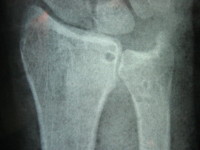

Οι απλές ακτινογραφίες συνήθως δεν είναι διαγνωστικές και απαιτείται διενέργεια μαγνητικής τομογραφίας για την επιβεβαίωση της κλινικής διάγνωσης.